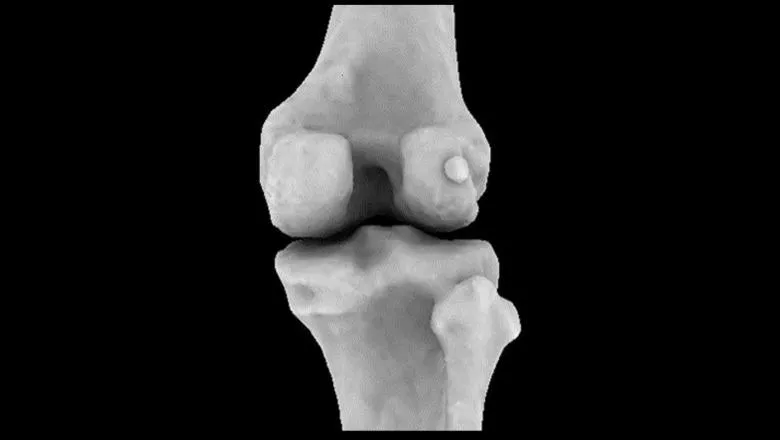

Боковая фабелла на задней поверхности колена человека – вид сбоку. Источник: Имперский колледж Лондона.

Сравнение задней части колена человека (слева) и макаки (справа), на котором видны медиальная и латеральная фабеллы у макаки и латеральная фабелла у человека. Фото: доктор Майкл Бертаум и Имперский колледж Лондона.